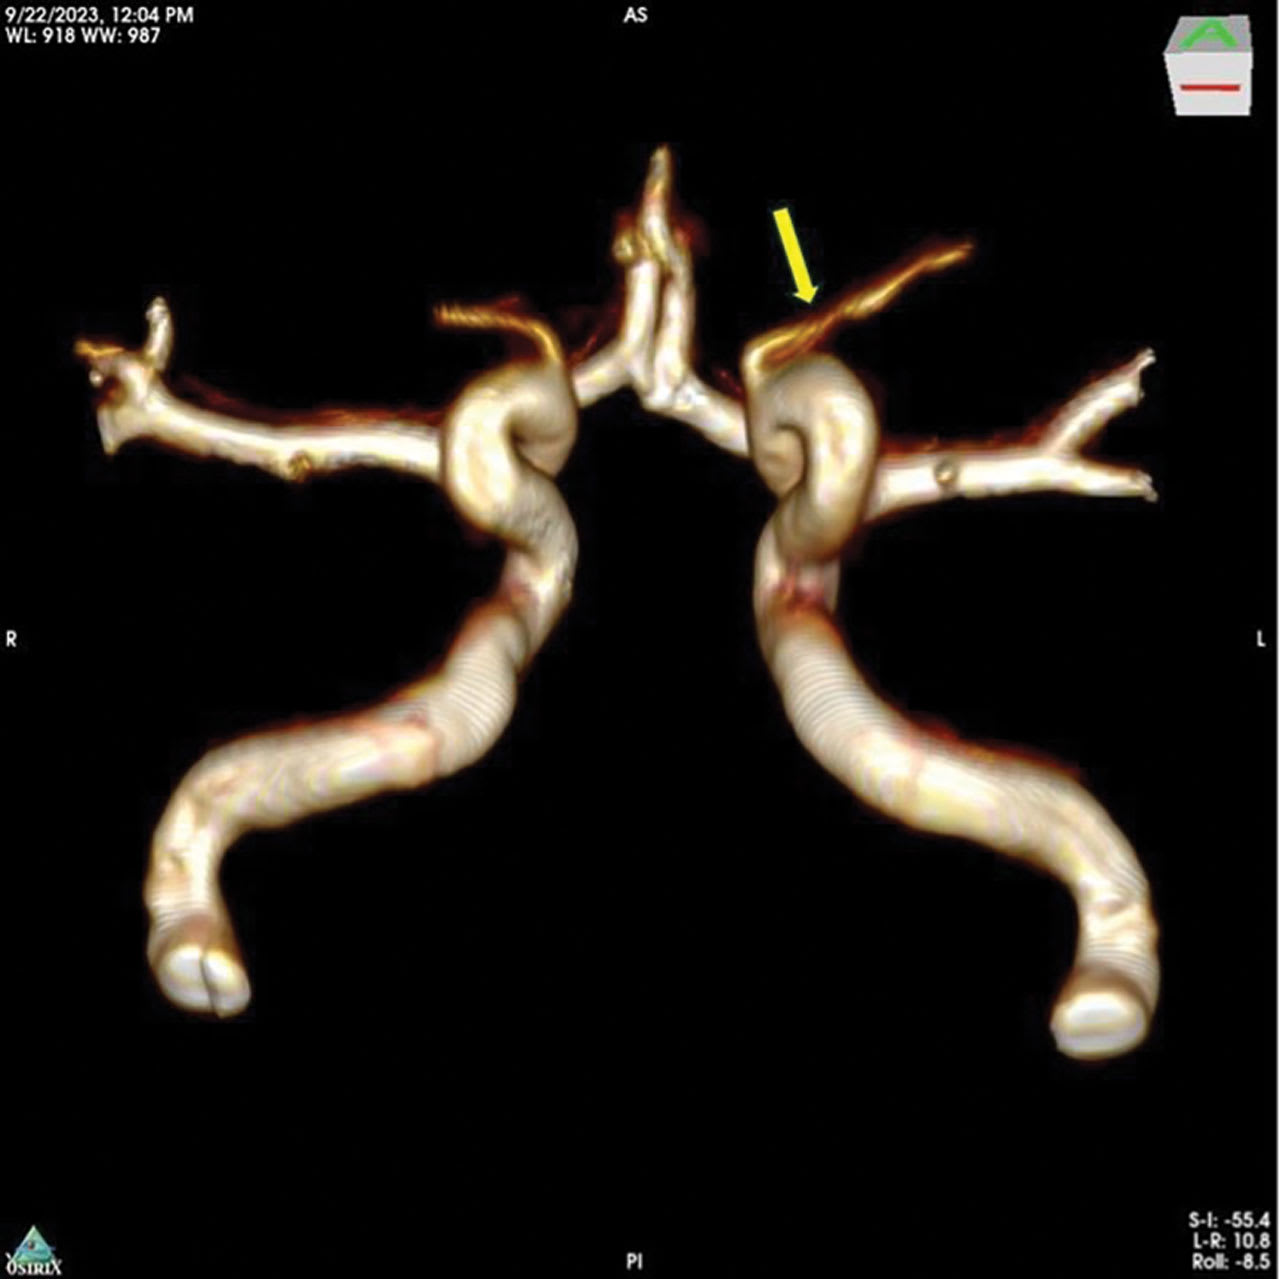

Figure 1. Magnetic resonance imaging angiography shows bilateral internal carotid arteries with ophthalmic artery segments demonstrating defuse stenosis in the long limb of the left ophthalmic artery (yellow arrow). Imaging performed with an Ingenia 3.0T magnetic resonance device (Philips NV). Image courtesy OcuDyne.

From an interventional neuroradiology perspective, the presence of OA stenosis was identified via screening MRI angiography (Figure 1) and confirmed with preprocedural digital subtraction angiography (Figure 2). Neurologic evaluations were completed before and after the procedure to monitor the subjects. The procedures were completed by an experienced interventional neuroradiologist under general anesthesia, using standard-of-care vascular access procedures, monitoring, and imaging. The study participants were admitted to the treating facility and observed for 18 to 36 hours after the procedure to ensure recovery and stability.